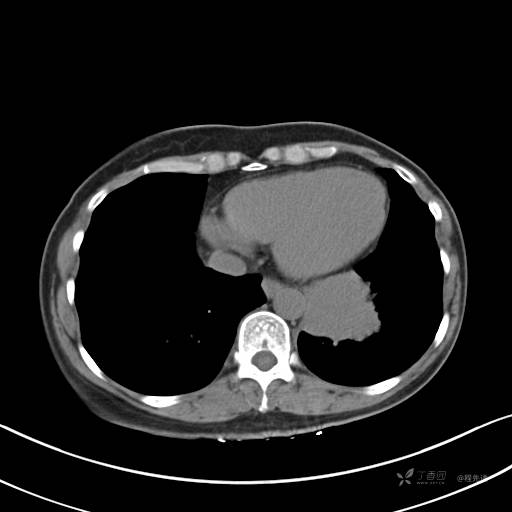

冠状位重建

CT值:平扫:31HU,动脉期:74HU,静脉期:84HU